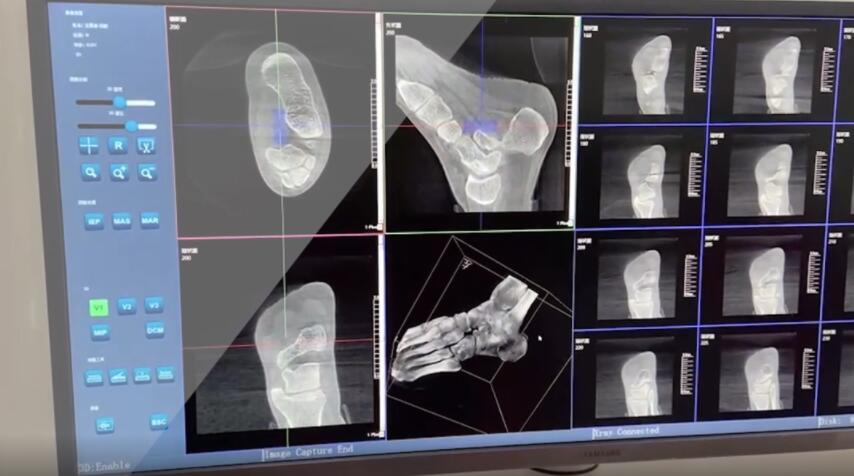

踝關(guān)節(jié)是人體中負(fù)重較大的關(guān)節(jié),也是活動(dòng)度較大的地方,所以對(duì)于足踝部位的關(guān)節(jié)內(nèi)骨折,我們更需要做到“解剖復(fù)位”。對(duì)于這種關(guān)節(jié)內(nèi)的骨折,尤其是踝關(guān)節(jié)內(nèi)部的骨折,不僅需要進(jìn)行X影像平片正側(cè)位的拍攝,由于在二維影像上無法判斷關(guān)節(jié)面的受損情況,往往還需要進(jìn)行三維影像的檢查。

在術(shù)前,我們需要做三維掃描的CT檢查,我們必須要有CT的片子,還要有三維的重建。

在術(shù)中,我們?cè)趺慈ヅ袛嚓P(guān)節(jié)面平不平整呢?常規(guī)的正側(cè)位影像是不能判斷的。有些醫(yī)生為了準(zhǔn)確的判斷,可能會(huì)選擇做開放性的手術(shù),把關(guān)節(jié)暴露出來,在眼睛的直視下判斷關(guān)節(jié)面平不平整。但是關(guān)節(jié)全部打開,無疑增加了病人的創(chuàng)傷,而且增加了患者的恢復(fù)時(shí)間。所以如果在術(shù)中我們有三維影像的支持,對(duì)醫(yī)生做手術(shù)而言就會(huì)事半功倍,而且能夠大大的增加手術(shù)準(zhǔn)確度,增加患者術(shù)后的預(yù)后。所以在術(shù)中有三維影像的支持是非常必要的!

三維影像? 看透關(guān)節(jié)內(nèi)骨折的“眼睛”